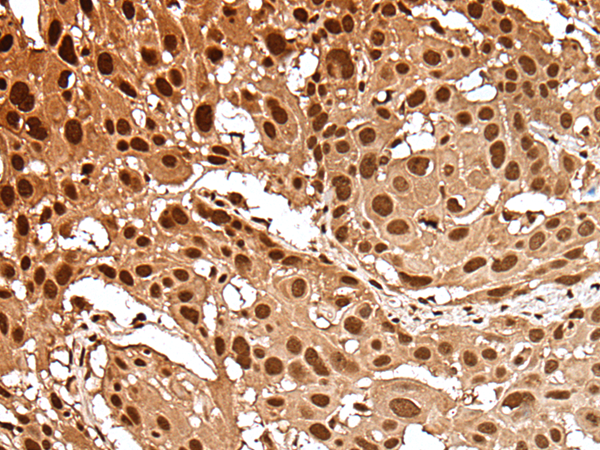

IHC positive control: |

Human esophagus cancer and human gastric cancer |

IHC Recommend dilution: |

25-100 |